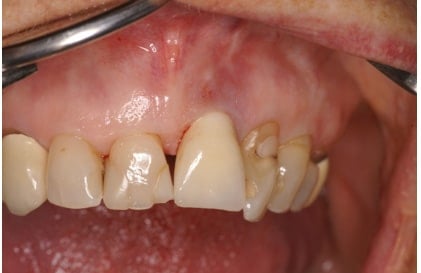

Situatie 2 jaar na chirurgie

De volgende evaluatie, na twee jaar, laat een stabiel en gezond parodontium / peri-implantair weefsel zien met een voortgaande verbetering van de botsituatie rond het implantaat 21 (status 5 + solo opname).

Bij de evaluatie op 11 mei 2017 wordt geconstateerd dat de doelstellingen zijn gehaald en er sprake is van een gezond peri-implantair weefsel met regeneratie van bot rond het implantaat (status 4 + solo opname).